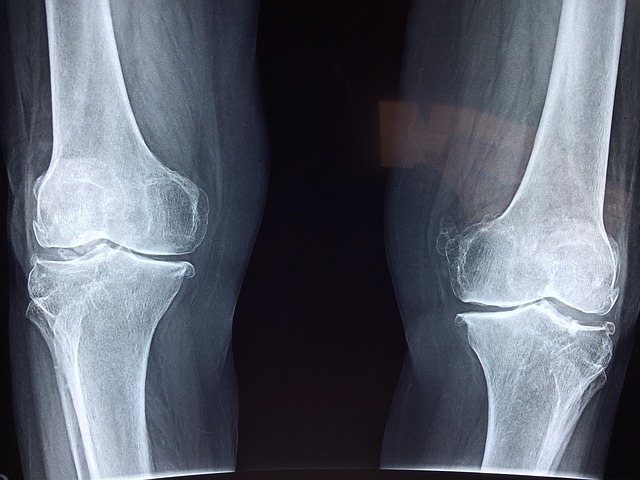

페이퍼 증후군(Paper Syndrome)은 유전적으로 뼈가 비정상적으로 단단해지는 희귀 골격 질환으로, 일반적으로 골강화증(Osteosclerosis)과 관련이 있습니다.

이 질환을 가진 사람들은 정상적인 뼈보다 훨씬 밀도가 높은 뼈를 가지게 되며, 이로 인해 유연성이 감소하고 골절 위험이 증가할 수 있습니다.

페이퍼 증후군의 정확한 원인은 아직 명확하게 밝혀지지 않았지만, 유전적 돌연변이가 주요 원인으로 추정됩니다. 뼈조직이 지속적으로 과도하게 형성되면서 신체의 골격 구조가 점점 더 단단해지고, 특정 부위에서는 움직임이 제한될 수도 있습니다.

페이퍼 증후군의 가장 큰 특징은 뼈가 비정상적으로 단단해지는 것입니다. 이는 겉보기에는 문제가 없어 보이지만, 실제로는 신체의 자연스러운 움직임을 제한할 수 있습니다.

특정 부위의 뼈가 지나치게 단단해지면서 관절이 뻣뻣해지거나 움직이기 어려워질 수 있습니다.

아이러니하게도, 뼈가 단단해질수록 골절 위험이 높아질 수 있습니다. 뼈가 너무 단단하면 외부 충격을 흡수하는 능력이 떨어지기 때문에 강한 충격이 가해질 경우 쉽게 골절될 수 있습니다.

정상적인 뼈는 파골세포(뼈를 분해하는 세포)와 조골세포(뼈를 만드는 세포) 간의 균형을 유지하지만, 페이퍼 증후군 환자는 조골세포의 활성이 과도하게 증가하여 뼈가 계속 단단해지는 현상이 나타날 수 있습니다.